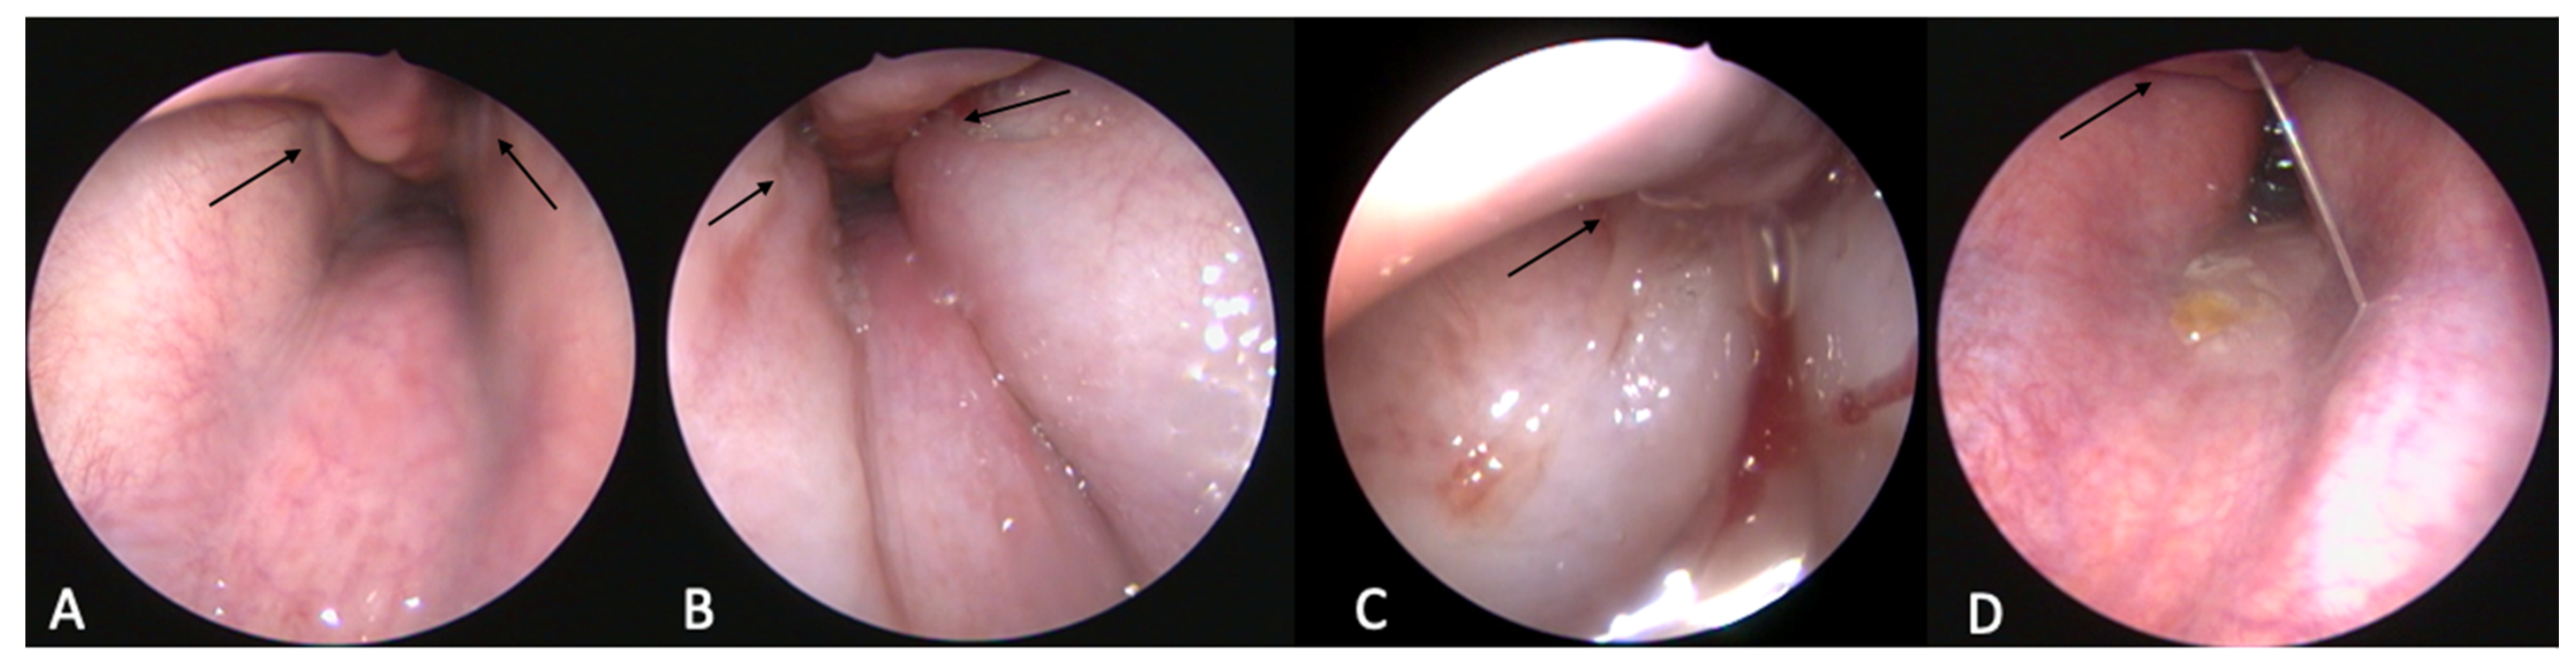

3.2.3. Tympanic Membrane

3.2.4. Imaging